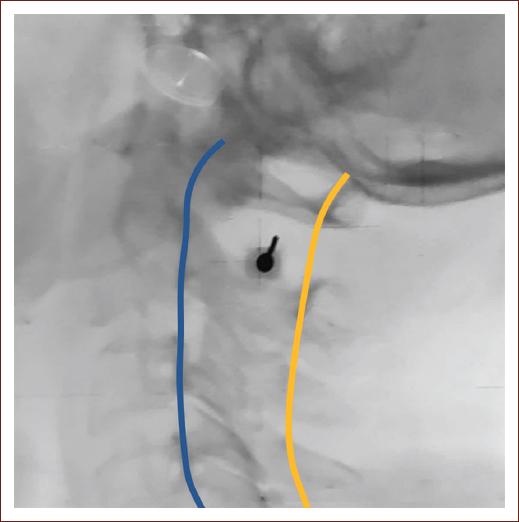

A 22 g needle was inserted medially using fluoroscopy guidance and continued to be advanced horizontally through planes of skin, connective tissue, trapezius, and occipital muscles; finally, resistance was encountered when reaching the dura mater. After penetrating the dura, it was advanced by 2 more millimeters, and the flow of CSF was verified. When no sample was obtained, the needle was repositioned caudally, making an angulation of approximately 30° (Fig. 1). It was verified again, and on verifying the successful exit of CSF, obtaining samples began (Fig. 2). A total of 25 mL of CSF was drained. Samples were sent for cytological and cytochemical studies and cultures, as well as a vial for storage in case, new tests were requested.

Figure 1 X-ray of the cervical spine showing the spinolaminar line in yellow and the posterior vertebral line in blue. Cervical puncture was performed near to the spinolaminar line, the needle is shown between them.